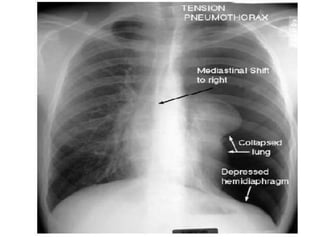

Definition

• Presence of air/gas in the pleural cavity/space is

known as pneumothorax.

Investigation

• X-ray –

1. Mediastinal shift

2. Absence of bronchovascular marking (lung

marking)

3. Reveal the Presence or absence of pleural fluid

• CT scan – recommended only in difficult cases

• Tension spontaneous pneumothorax –

1. Pleural tear act as a ball and valve mechanism

2. Pleural cavity pressure is more than atmospheric

pressure

3. Progressive breathlessness

4. Central cyanosis

5. Peripheral circulatory failure